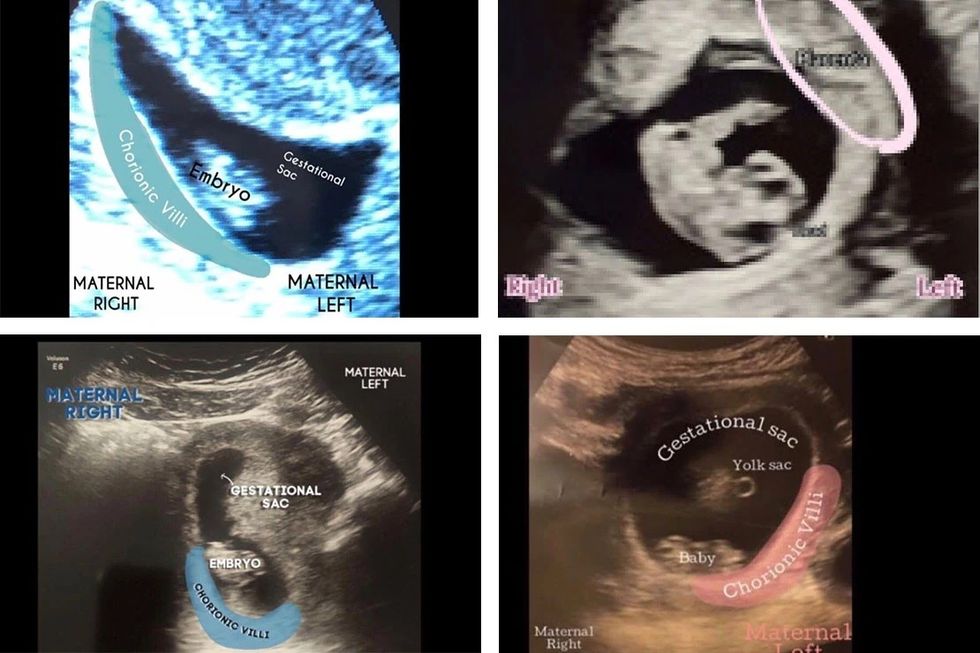

* Pasi të bëni ekon e parë (zakonisht rreth javës së 6-të ose 8-të), pyesni mjekun për vendndodhjen e placentës.

* Mbani mend që në fazat e hershme të shtatzënisë, placenta mund të mos jetë formuar plotësisht dhe të jetë e vështirë për t’u dalluar.